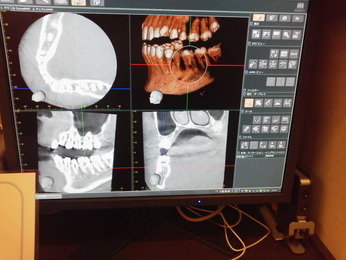

他の都心の矯正歯科で治療中で、ほぼ終了近くの方でした。歯並びで言えば上下の歯が突出していて唇が閉じにくいというのをなんとかしたい。そして歯を抜かないで出来るところを探して都心の矯正歯科への通院となりました。ところが本人曰くよく噛めないというのです。

相談しても“問題無い”の説明だけだそうです。調べたところ歯周病は進行しているし、奥歯の大きい歯2本ずつ計4本はしっかり噛んでいないのです。よく噛めないというのはそのことのようでした。これを矯正的に元に戻すことはできない訳ではありませんが、時間と手間がかかるのは間違いないことです。